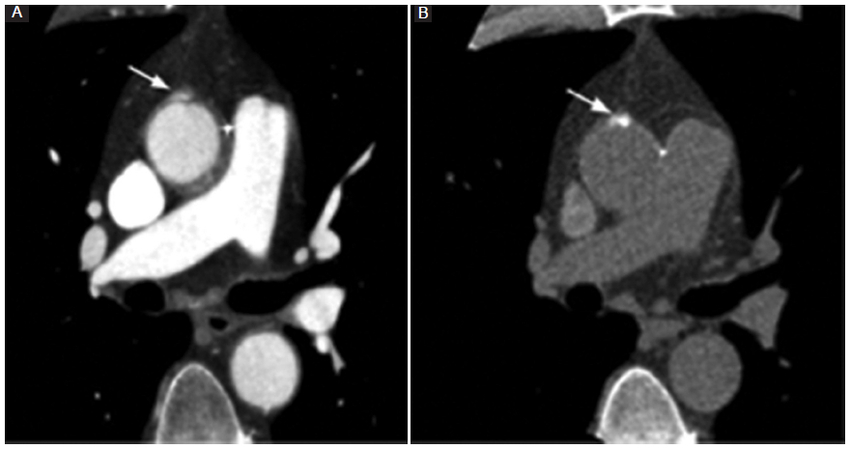

La fase sin contraste es de vital importancia para diferenciar las estructuras posquirúrgicas hiperdensas normales de las posibles complicaciones, como son la extravasación del material de contraste y los pseudoaneurismas. El dacrón es el material empleado en las prótesis y se observa de bordes redondeados, paredes lisas y ligeramente hiperdenso en las fases sin contraste intravenoso, lo cual puede simular un pseudoaneurisma. Este último se diferencia por su presentación típica en forma de lesiones hipodensas o isodensas en las imágenes sin contraste (Fig. 8) (3,4,5,6,7,8.

Otro dato a tener en cuenta son las tiras de fieltro que pueden verse alrededor del injerto, como en los sitios de colocación de la cánula arterial, al igual que el lugar de la anastomosis de la arteria coronaria (técnica del botón) (Fig. 9). Estas tiras también se observan espontáneamente densas en las fases sin contraste, pudiendo asemejar extravasación del contraste o un pseudoaneurisma (Fig. 10) (8. Otra manera de diferenciar un pseudoaneurisma es la ubicación, debido a que las tiras de fieltro y de dacrón suelen encontrarse a lo largo de toda la circunferencia de la anastomosis, mientras que un pseudoaneurisma estaría ubicado excéntrico a lo largo de una sola pared. En las fases poscontraste, el injerto suele ser indistinguible de la pared nativa8.

Los pseudocolgajos son visualizados como una banda lineal hipodensa generada por una leve angulación del injerto, en ocasiones confundido con una disección aórtica real, al no ser examinado en múltiples planos (Fig. 11) (8.

Por último, las áreas de realce u ocupación en el espacio generado entre la raíz del injerto y la envoltura aórtica nativa circundante, así como en la anastomosis del botón de la arteria coronaria, pueden hacer sospechar una dehiscencia o una rotura. Sin embargo, en las técnicas de inclusión, como la de Cabrol, pueden visualizarse con relativa frecuencia y se consideran como hallazgos esperables en el contexto clínico de un paciente asintomático. Pueden persistir sin modificaciones imagenológicas por un largo periodo de tiempo (Fig. 12) (9.